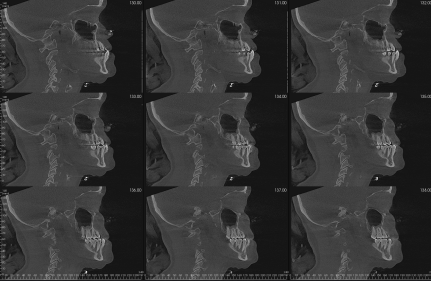

axial sections

coronal sections

saggital slicing

transaxial sections